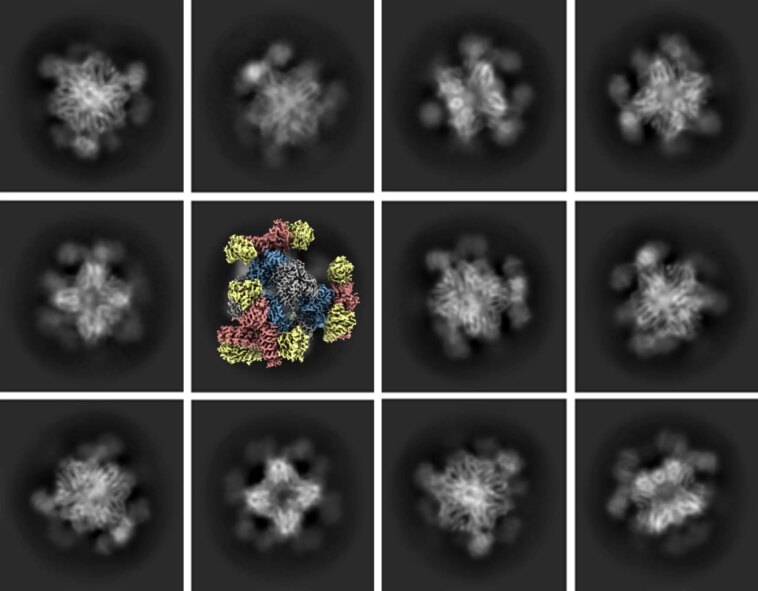

Une série d’images cryo-EM. Les photos en niveaux de gris représentent des projections 2D de plusieurs vues de l’échafaudage d’imagerie attaché à une protéine cible ; l’image couleur illustre la reconstruction 3D dérivée de projections 2D. Crédit : Roger Castells-Graells/UCLA

Aujourd’hui, des biochimistes de l’Université de Californie à Los Angeles (UCLA), en collaboration avec des scientifiques de l’industrie pharmaceutique, ont développé une solution qui permettra également à la cryo-EM d’acquérir des images de haute qualité de molécules protéiques plus petites. Les scientifiques ont conçu une structure protéique en forme de cube de 20 nanomètres, appelée échafaudage, avec des saillies rigides en forme de trépied qui maintiennent les petites protéines en place.

L’échafaudage peut être numériquement supprimé de l’image lors du traitement de l’imagerie, laissant une image composite 3D des petites protéines analysées par les scientifiques.

En cryo-EM, les scientifiques utilisent un microscope cryoélectronique pour envoyer un faisceau d’électrons à travers des échantillons de matériau congelés, laissant derrière eux une image des milliers de molécules, telles que des protéines, présentes dans l’échantillon. Les molécules sont photographiées exactement telles qu’elles se trouvent dans l’échantillon, produisant des milliers de photographies 2D de la molécule prises sous différents angles. Le traitement informatique réconcilie toutes ces photographies pour formuler une image 3D correcte – en séparant l’arrière-plan, en regroupant les images avec des orientations similaires et en générant une image 3D haute résolution d’une seule molécule.

Mais lorsqu’il s’agit d’imager les plus petites molécules de protéines, leur petite taille rend impossible la détermination de leurs orientations dans les images, ce qui donne des images de résolution relativement faible.

Dans des études précédentes, les scientifiques avaient tenté de résoudre le problème en attachant de petites molécules à des échafaudages plus grands, mais ces expériences ont démontré que si les petites molécules étaient attachées de manière trop flexible, elles dépasseraient de l’échafaudage sous différents angles et orientations, ce qui produirait toujours des images floues. .

Dans la nouvelle étude, l’échafaudage créé par les scientifiques comporte des saillies en forme de trépied qui capturent les protéines et les maintiennent fermement en place, ce qui donne les images à plus haute résolution qu’elles recherchaient.

« La fixation rigide des petites molécules à des échafaudages plus grands crée des particules suffisamment grandes pour être imagées et qui ont toutes exactement la même forme 3D », a déclaré Yeates. « Et à partir de là, le processus fonctionne comme d’habitude pour construire l’image 3D haute résolution. »